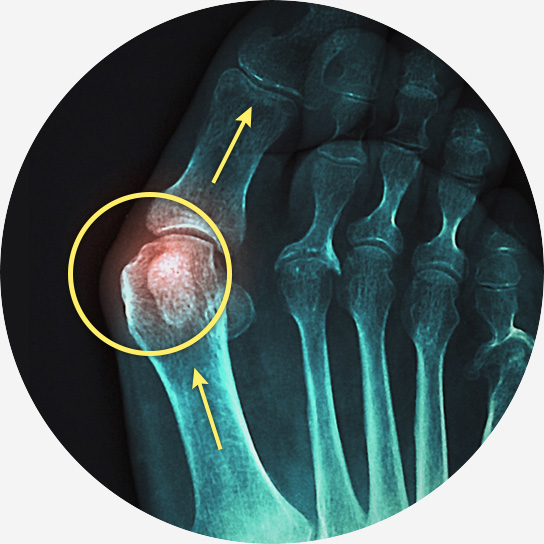

무지 외반증은 엄지발가락이 두 번째 발가락 쪽으로 휘어지면서 발 안쪽으로 튀어나오는 질환입니다.

엄지발가락 관절 부위가 붓고 염증이 생겨 통증을 유발하며, 심한 경우에는 걷거나 서 있는 것조차 힘들어질 수 있습니다.

엄지발가락이 두 번째 발가락 쪽으로 휘어짐

엄지발가락 관절 안쪽이 튀어나오고 통증 발생

튀어나온 부위의 발적, 부종, 굳은살